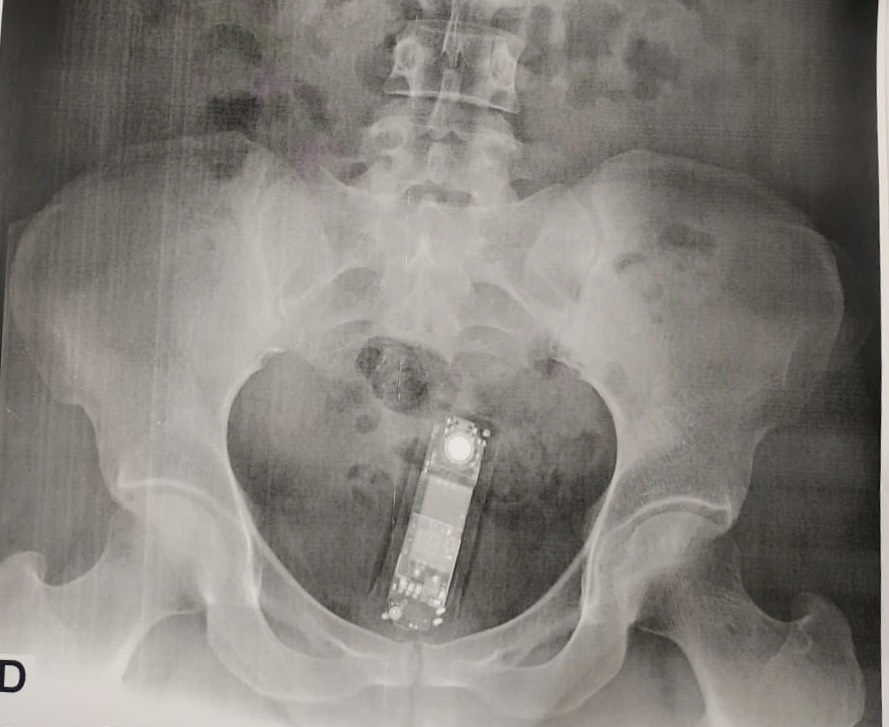

No último sábado, 16, uma senhora identificada como E. N. L., 39 anos, foi flagrada tentando entrar com um mini celular de seis centímetros na Casa de Prisão Provisória de Palmas (CPPP), ela pretendia entregar o celular para o filho preso na unidade. Com este, são nove casos de mulheres presas em flagrante por tentar adentrar ilícitos na carceragem. Os casos foram identificados através de equipamentos de segurança, preparo dos agentes prisionais e estratégias da equipe de inteligência.

O procedimento que levou à prisão dessas nove mulheres é muito parecido com o adotado no flagrante de E. N. L. De acordo com o diretor da CPPP, Thiago Oliveira Sabino, a mulher passou pelo pórtico detector de metal, teve os objetos escaneados em um raio-x e foi liberada para o próximo ponto de revista. “Ela foi encaminhada para uma sala individual, lá a agente passa a raquete detectora de metal no corpo e nos calçados, depois tem que sentar na banqueta, que também é utilizada para detectar metal. Quando ela sentou na banqueta, a máquina sinalizou que ela carregava algo metálico consigo”, explicou.

Após, a mulher confessou as agentes que carregava um celular na genitália e foi conduzida para a Unidade de Pronto Atendimento Norte, em Palmas, para retirada do aparelho. “Depois de confirmada a presença do celular no raio-x, o médico realizou a retirada e ela foi levada para a Delegacia de Polícia para o registro de ocorrência”, informou Sabino.